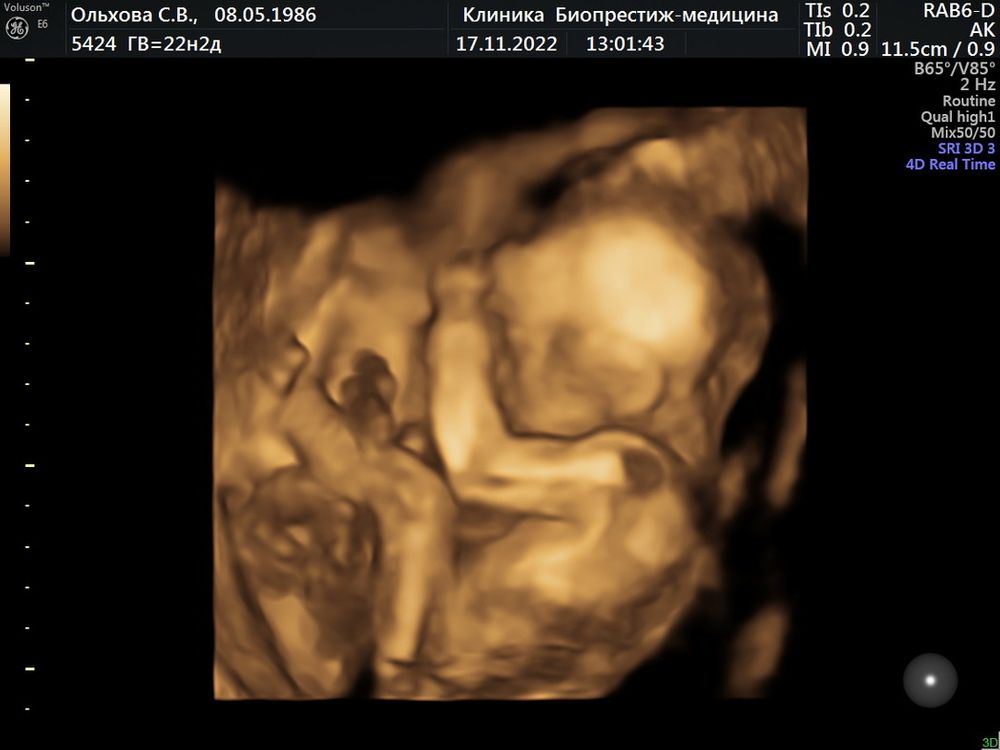

Алина, 3 д там не много он смотрит. Надо прям уточнять. Но фото высылают и дают. Даша сегодня вот. Изображение